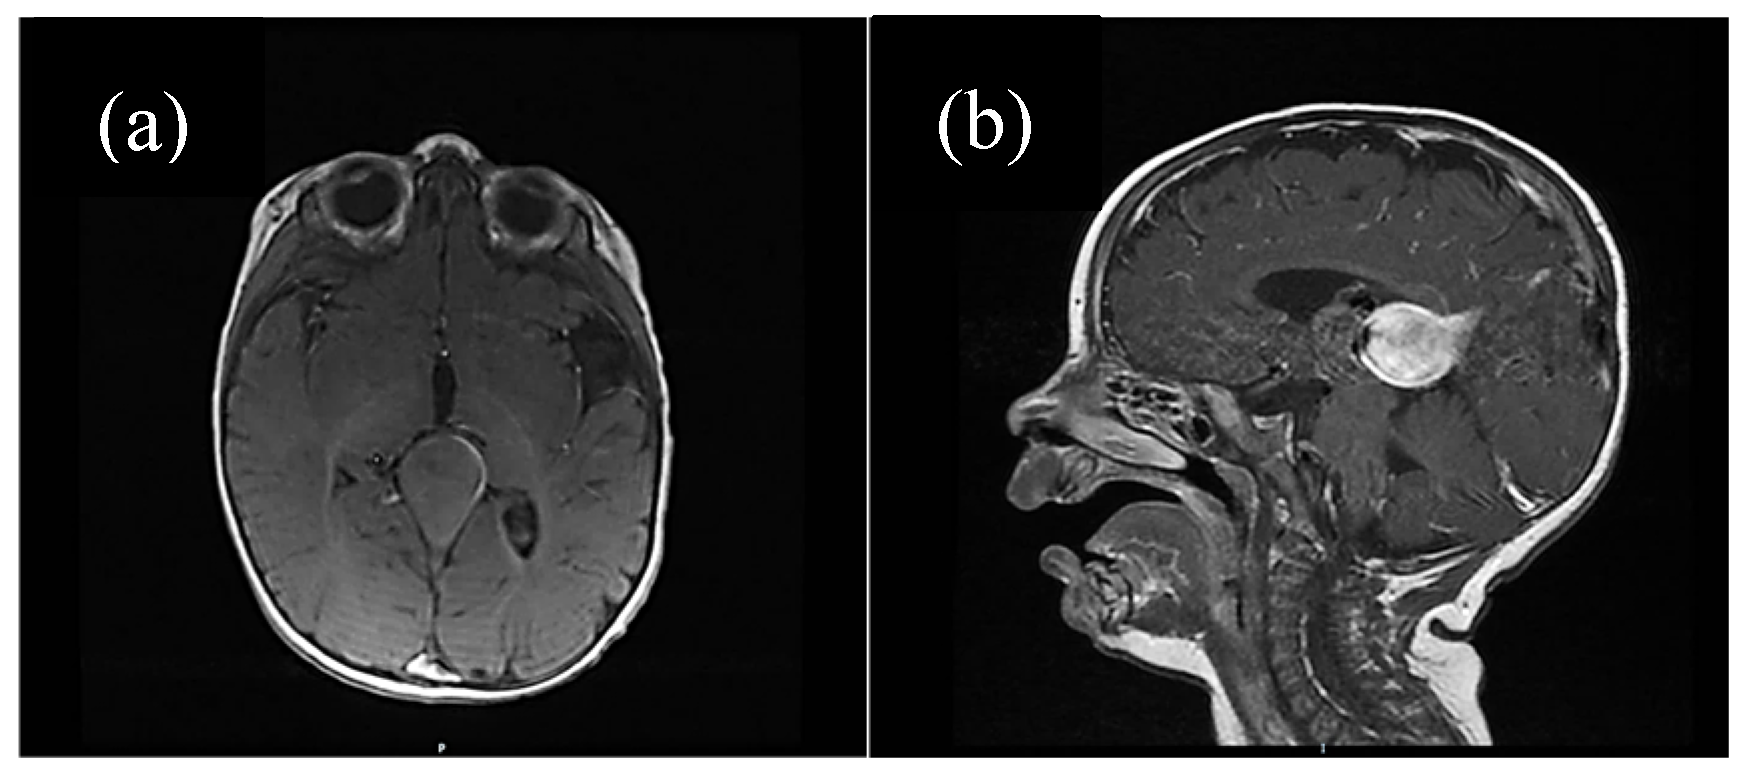

For some patients, the diagnosis was completed by brain MRI cerebral angio-CT (with iodinated radiocontrast agent at a concentration of 300 mg I/mL) methods for a better understanding of the Galen vein aneurysm morphology and its anatomical relations (see Figure 3, Figure 4, Figure 5 and Figure 6). Three of five patients who performed superior imaging techniques had large varieties of the Galen vein malformation, with variable degrees of compressive effect and secondary changes in the appearance of the midline and ventricular symmetry. Three patients presented with corpus callosum dysgenesis and three others with engorged arteries of the Willis polygon and enlarged pericerebral venous sinuses. None of the patients underwent an angiographic study of the arteriovenous malformation they had been diagnosed with in order to conceivably facilitate the perspectives of endovascular embolization in a center with expertise.

Figure 3. (a) Native cerebral MRI (transverse section), (b) contrast cerebral IRM (sagittal section). Vascular aneurysmal dilation at the level of the quadrigeminal tank, with no significant compressive effect, no thrombosis, no infra/supratentorial lesions. Asymmetrical ventricular system but normally positioned midline structures. Ependymal cyst located in the atrium of the LV. Asymmetry of the temporal lobes due to incomplete gyration.